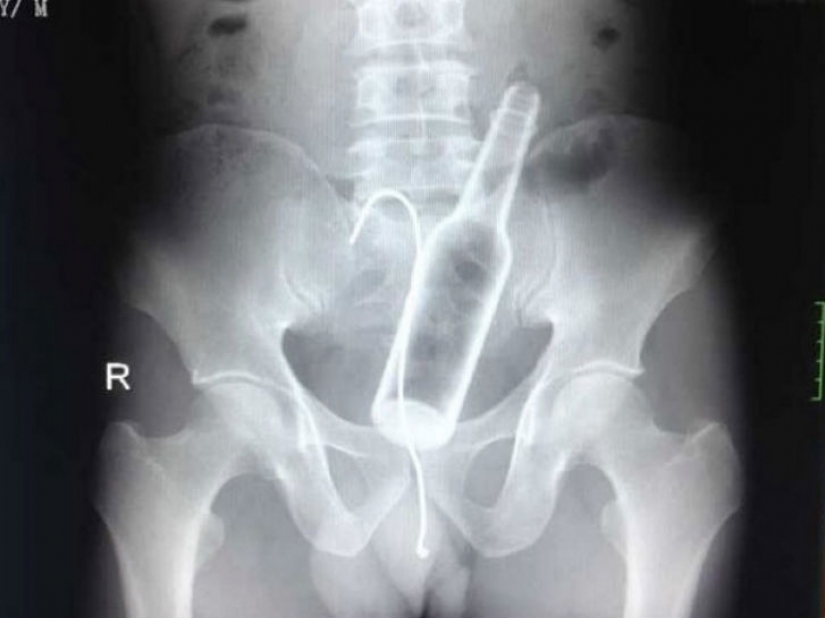

Uno de los hospitales Chinos, vino un hombre con quejas de dolor abdominal. Los médicos tomaron una radiografía y se encontró una botella de vidrio en el estómago.